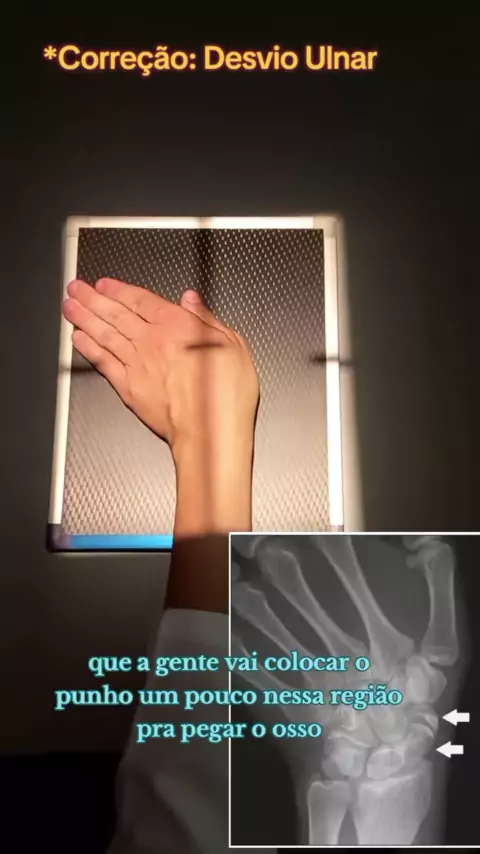

Caso do dia - Fratura no punho necessitando a colocação dos fios de Kirschner. Créditos: Dr. Murilo Carpes #traumatologia #emergência #cirurgia #fiosdekirschner #fisioterapia

Posicionamento do punho em 1 minuto ☢️ #radiologia #xray #ortopedia #viral #técnicoemradiologia